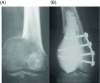

Giant cell tumor (GCT) of bone is a locally aggressive benign neoplasm that is associated with a large biological spectrum ranging from latent benign to highly recurrent and occasionally metastatic malignant bone tumor. It accounts for 4-10% of all bone tumors and typically affects the meta-epiphyseal region of long bones of young adults. The most common site involved is the distal femur, followed by the distal radius, sacrum, and proximal humerus. Clinical symptoms are nonspecific and may include local pain, swelling, and limited range of motion of the adjacent joint. Radiographs and contrast-enhanced magnetic resonance imaging (MRI) are the imaging modalities of choice for diagnosis. Surgical treatment with curettage is the optimal treatment for local tumor control. A favorable clinical outcome is expected when the tumor is excised to tumor-free margins, however, for periarticular lesions this is usually accompanied with a suboptimal functional outcome. Local adjuvants have been used for improved curettage, in addition to systematic agents such as denosumab, bisphosphonates, or interferon alpha. This article aims to discuss the clinicopathological features, diagnosis, and treatments for GCT of bone.